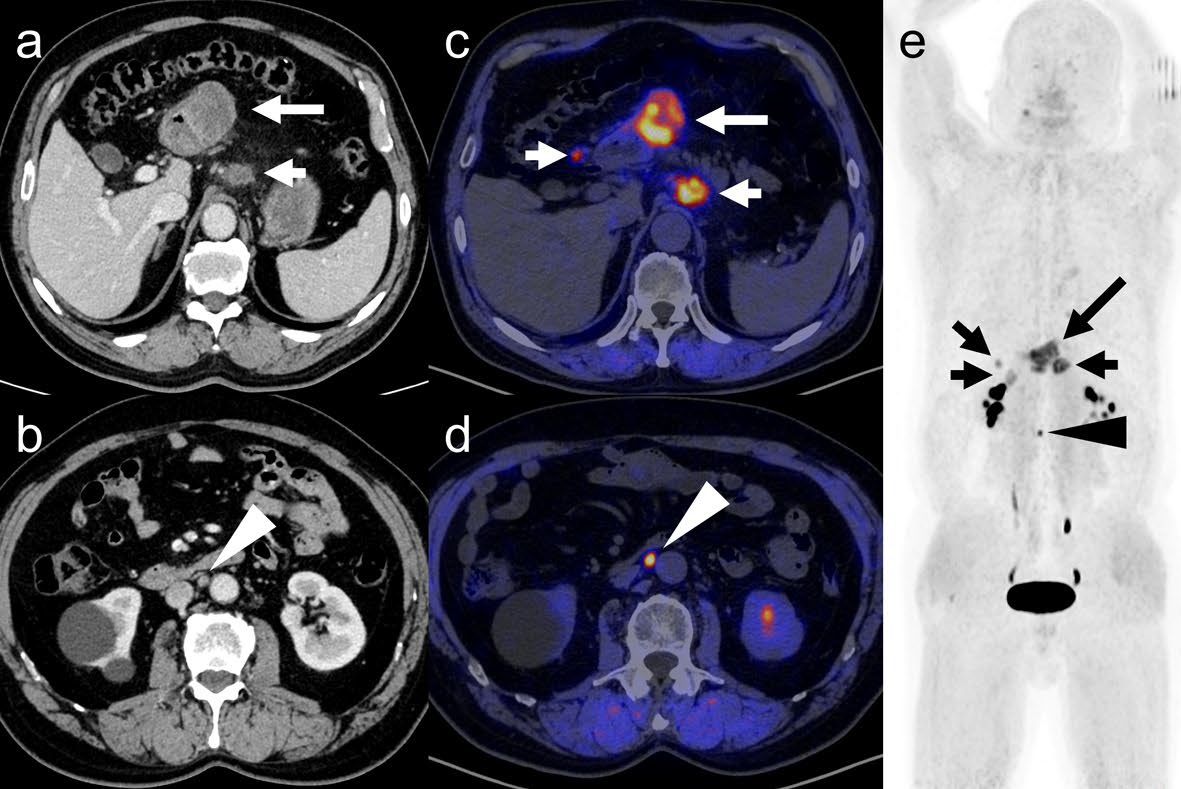

Additionally, F-18 FAPI demonstrated significantly higher sensitivity values in detecting unsuspected regional lymph node metastases on patient- and lesion-based analysis, as well as finding distant metastases on lesion-based analysis.

| Detecting URNM | 52.4% | 97.6% | < 0.001 |

| Detecting distant metastases | 67.3% | 98.1% | < 0.001 |